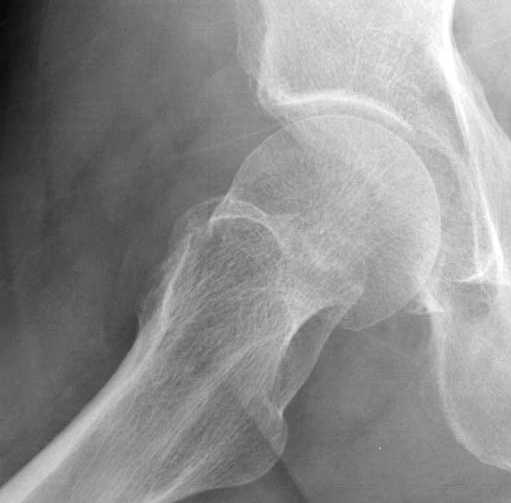

Почему неполный перелом? Я бы назвал его вколоченным!

Перелом конечно не вколоченный т.к. видно линию перелома и нет суперпозиции костной ткани.

Добрый день. Перелом коварный. Через время может произойти лизис в области "неполного" перелома и он превратиться в "полный" со всеми очевидными проблемами, тем более у пациента, склонного к питию. Если не разовьется делирий или после выхода из него, рекомендую внутренний остеосинтез винтами.

Профилактику дальнейшего раскола неполного перелома шейки провели тремя канюлированными шурупами.

И вне контекста, еще...по классификации Devas cтрессовые переломы шейки разделяются на тензионные и компрессионные. У молодых обычно происходит по типу компрессионных переломов, они более стабильные, а у пожилых по типу тензионных (дистракционных) переломов.

Молодым дисциплинированным больным можно рекомендовать щадящее консервативное лечение на костылях. Критерием являются несмещенные переломы с обязательным частыми рентгенгенологическими наблюдениями. (См. приложенный алгоритм)

Снимок сустава с внутренней ротацией покажет абнормальную шейку, хотя золотым стандартом является Магнитно-резонансая томография.